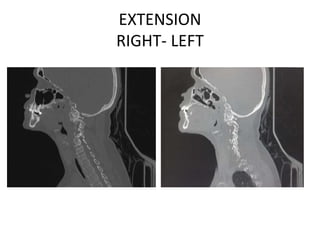

M Ramanamma is a 48-year-old female who presented with neck pain and paresthesias in her limbs for the past 5 months. On examination, she had decreased strength in her right upper and lower limbs and hypertonia in her lower limbs. Imaging showed atlantoaxial dislocation with compression of the cervical spinal cord at C1-C2, explaining her symptoms.